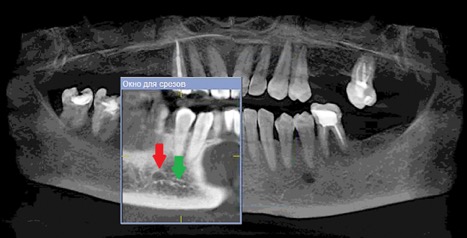

Данные осложнения происходят из-за повреждения резцовой петли – внутрикостного продолжения нижнелуночкого нерва (Рис. 1a и 1b), которая начинается от ментального отверстия и заканчивается индивидуально, как правило, на уровне латерального или центрального резца [1].

Рисунок 1а: КЛКТ. Панорамный реформат.

(Зеленая стрелка – резцовая петля, красная стрелка – подбородочное отверстие.)

Рисунок 1b: КЛКТ. Коронарный реформат нижней челюсти в переднем отделе.

(Зеленая стрелка – резцовая петля)